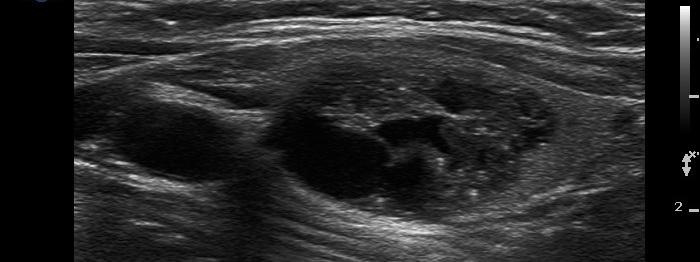

Metastasis of a kidney carcinoma to the thyroid - case 1574 |

Benign hyperplastic nodule (histological diagnosis) - case 1582 |

Both images show one relatively large granule which correspond to punctate echogenic foci.

Parts of the hyperechogenic granules are located in cystic area, while others are found in the solid part of the lesion. The latter might be punctate echogenic foci.